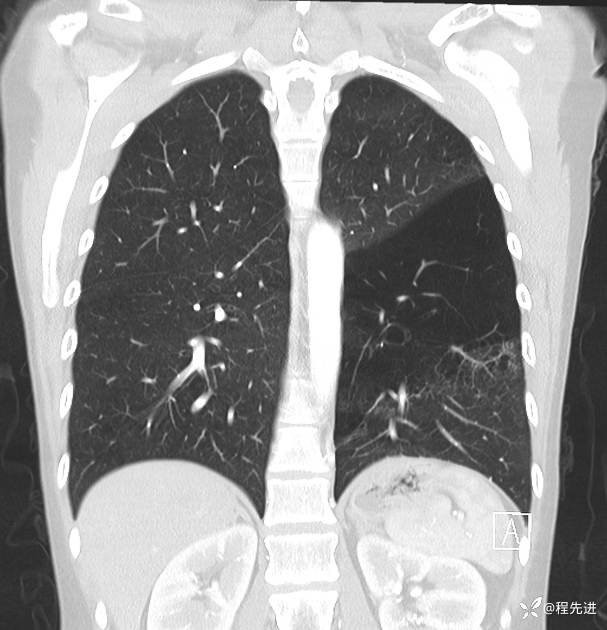

患者性别:女

患者年龄:25岁

简要病史:下胸部疼痛3天

DR:

img